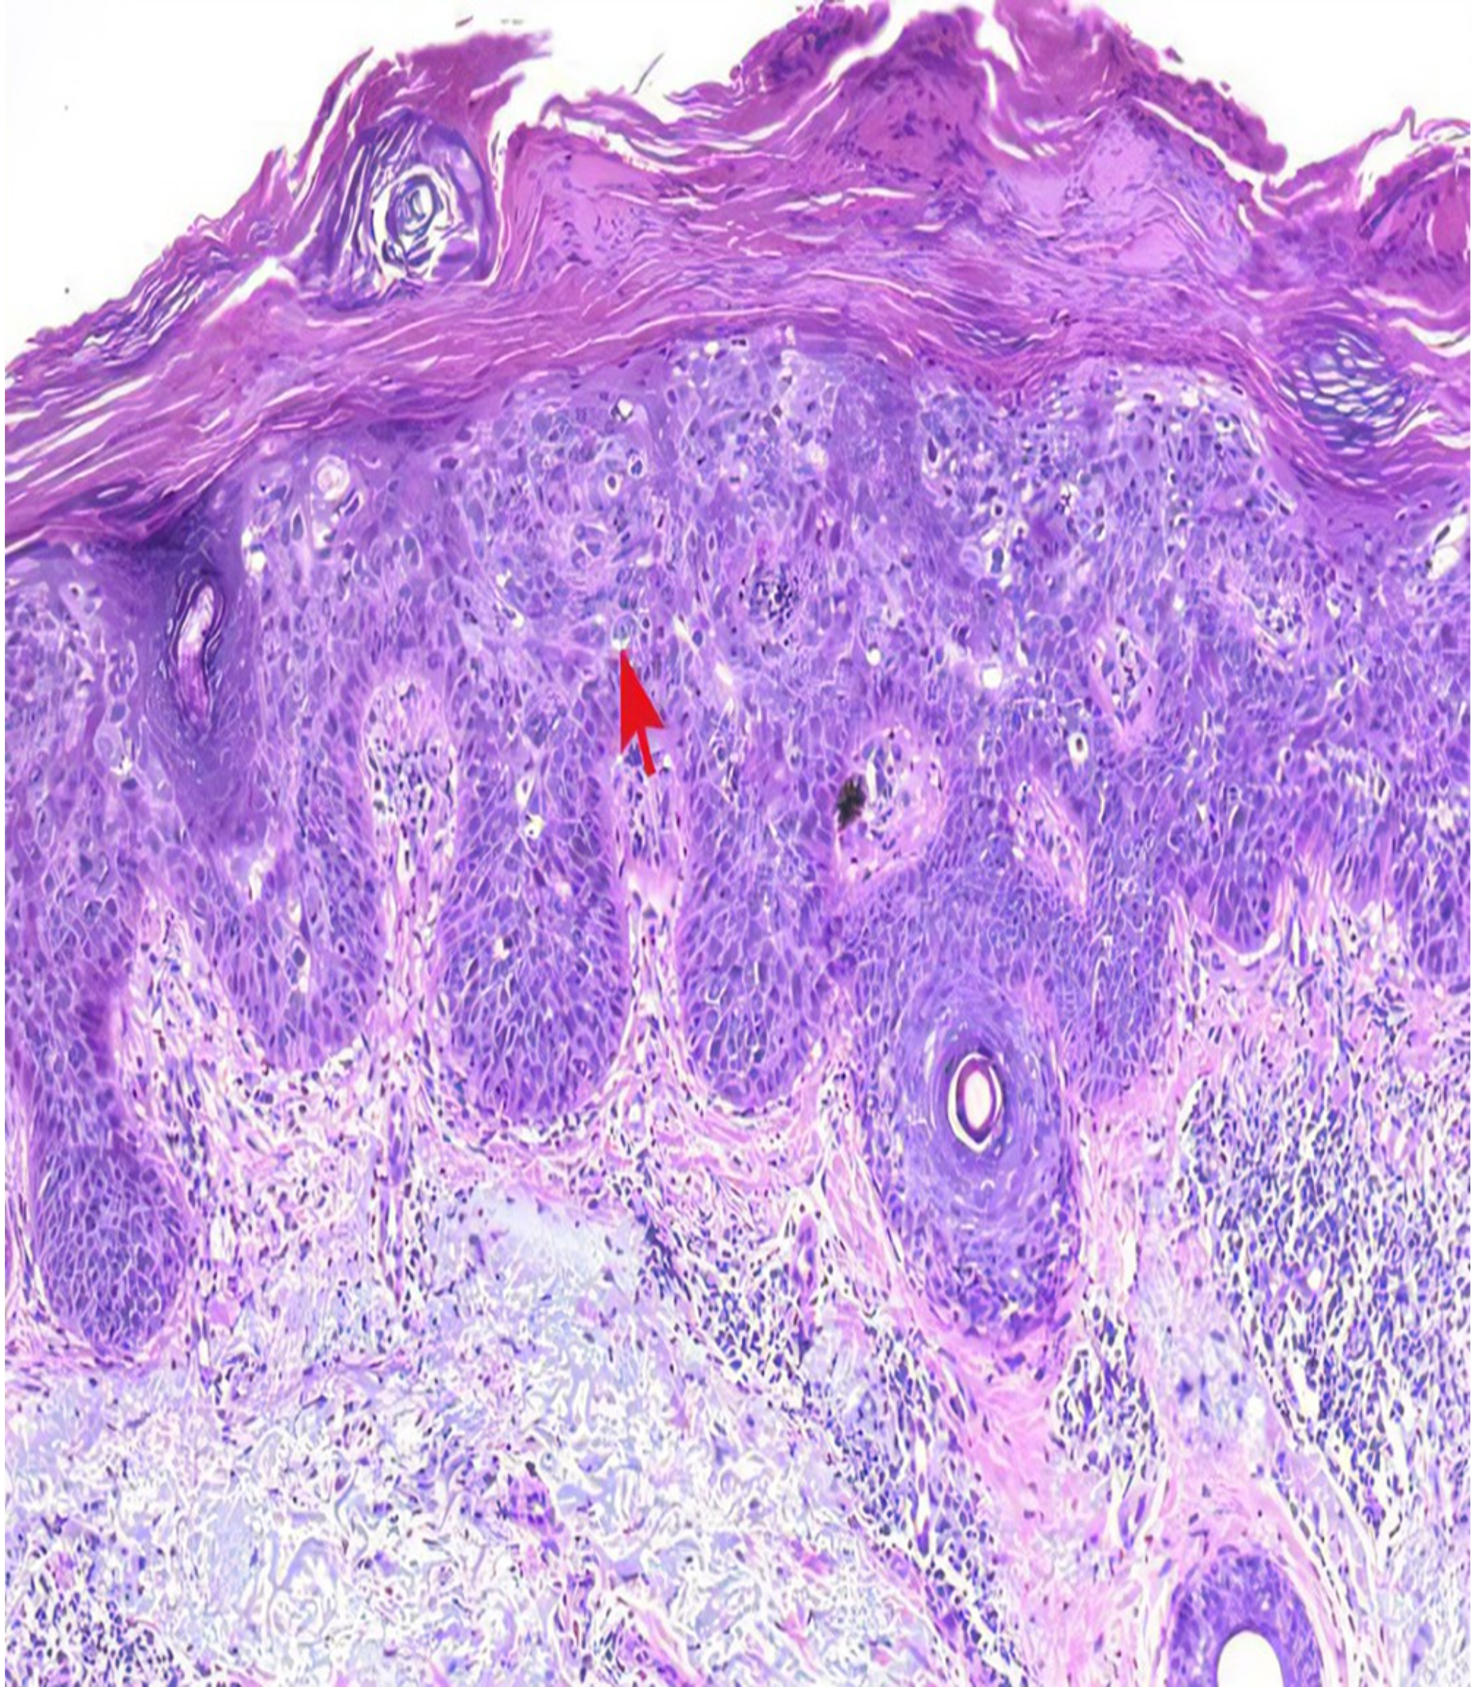

L’étude pharmacodynamique : régénération et réparation tissulaire

• Des lésions cutanées et musculaires sont provoquées, puis nous administrons le produit sous forme de crème en application cutanée ou par d’autres voies (intrapéritonéale, orale…).

• Des observations macroscopiques et microscopiques des tissus seront réalisées.